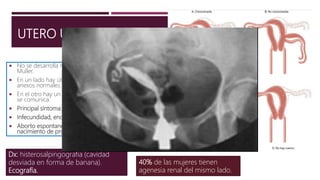

UTERO UNICORNE

 No se desarrolla ni elonga uno de los conductos de

Muller.

 En un lado hay útero funcional, cuello uterino normal y

anexos normales.

 En el otro hay un cuerno uterino rudimentario, que no

se comunica.

 Principal síntoma: dolor unilateral cíclico.

 Infecundidad, endometriosis y dismenorrea.

 Aborto espontaneo (36%), parto prematuro (16%) y

nacimiento de producto vivo (54%).

Dx: histerosalpingografia (cavidad

desviada en forma de banana).

Ecografía.

40% de las mujeres tienen

agenesia renal del mismo lado.